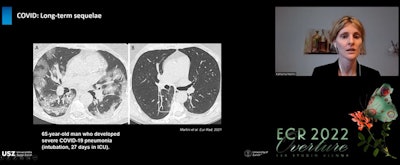

Remaining CT abnormalities are reported in 15% to 90% of COVID pneumonia patients at three months post discharge, the higher range being reported in patients previously admitted to the intensive care unit. But it is expected that these signs will reverse in the vast majority of cases. Besides largely resolved low attenuation GGO, in these patients, follow-up imaging might show other fibrotic-like findings such as linear consolidation, parenchymal bands, and perilobular opacities consistent with organizing pneumonia as well as reticulation, interstitial thickening, and bronchial distortion.

At three months post discharge, fibrotic-like changes, seen in the late stage of COVID-19 pneumonia, are reported in 21% to 26% of patients. In these cases, it is important to word findings carefully, and the difference between fibrosis and what is "fibrotic-like" must be clear for fear of overestimating them, Martini told listeners, While the latter can be precursors to fibrosis, there is a high probability these changes will resolve with time.

"The term traction bronchiectasis, suggesting irreversible fibrotic changes, should be used with caution. It's better to use the term bronchial distortion or bronchial dilatation," Martini noted. "Honeycombing is also an uncommon finding in COVID-19. If we see it, it is more likely that the patient has a pre-existing fibrotic lung disease than it being due to COVID."

At 12-month follow-up, most changes have resolved with only 24% of patients showing abnormal CT findings, and the spectrum of these findings also changing, noted Martini. Typical fibrotic-like features such as interlobular septal thickening and reticular opacity almost disappear by month nine to leave only GGO as the predominant residual finding. Established fibrosis or interstitial thickening is not observed.